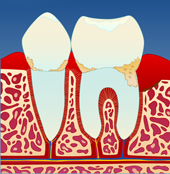

Mangelfullt renhold kan gi en overfladisk betennelse i tannkjøttet ( gingivitt ). Tannkjøttet blir da hovent og får en mørkere rødfarge. Det vil også blø ved berøring og føles ømt. Dette skyldes bakterier og mykt belegg som blir liggende langs tannkronen (I).

figur I figur II figur III figur IV

Dersom belegget ikke fjernes, vil det over tid forkalkes og bli hardt. Det er dette vi kaller tannstein. Tannstein forsterker betennelsen som fører til at benet rundt tennene brytes ned (II). På denne måten vil tannstein og bakteriebelegg kunne strekke seg stadig lenger ned langs rotoverflaten (III). Bentapet kan over tid bli så omfattende at tenner løsner og eventuelt må fjernes (IV).